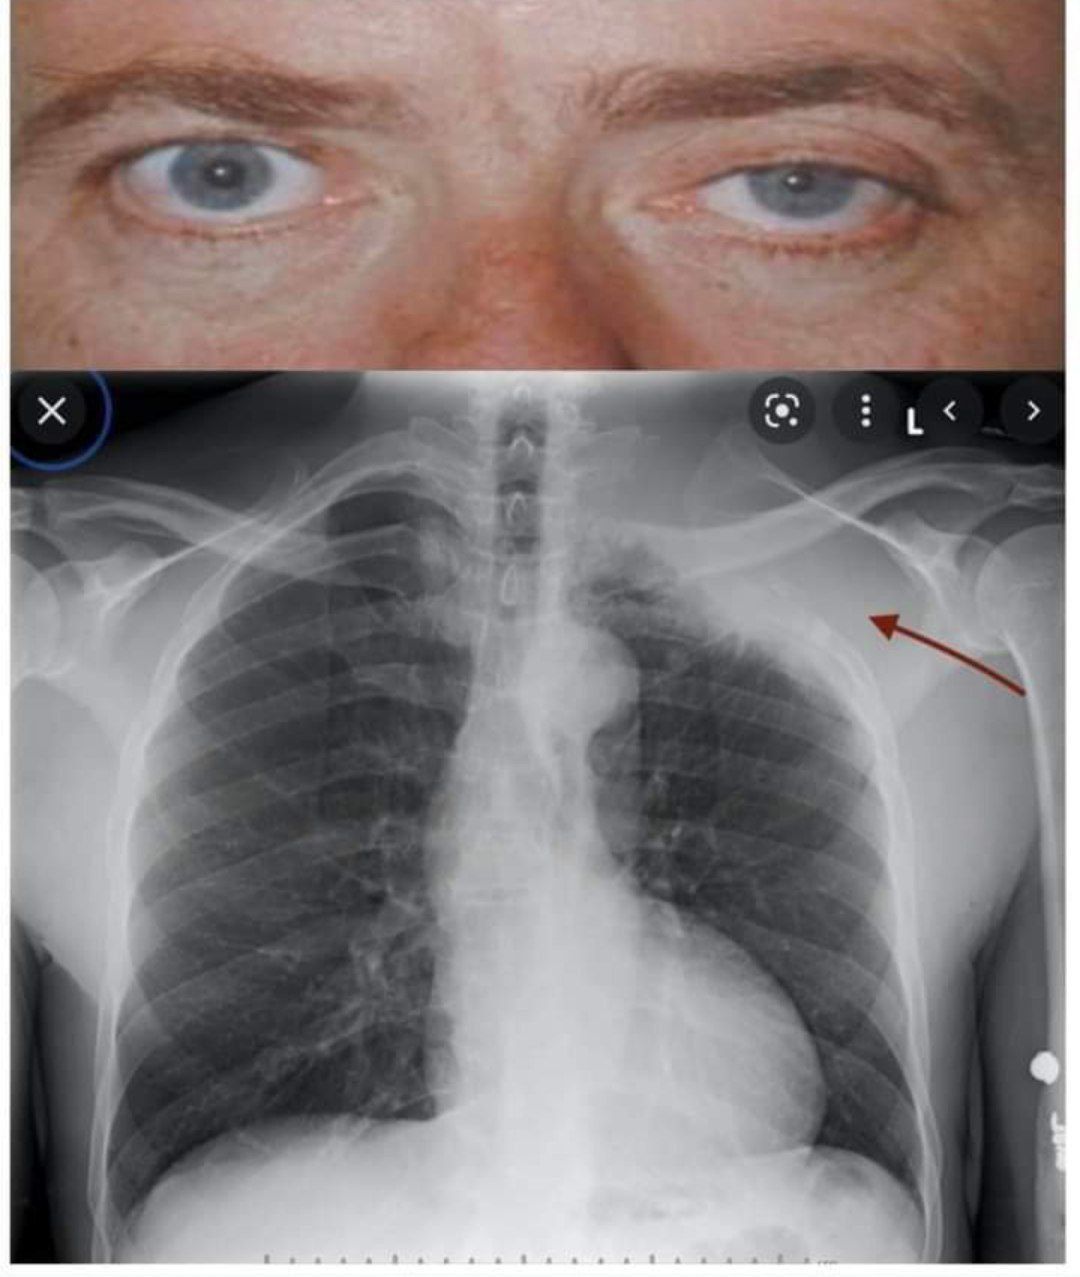

Pancoast tumor cause horner,s syndrome

• Pupillary size difference • The affected eye is sunken • drooping upper eyelid • Bangkokist tumor at the top of the lung